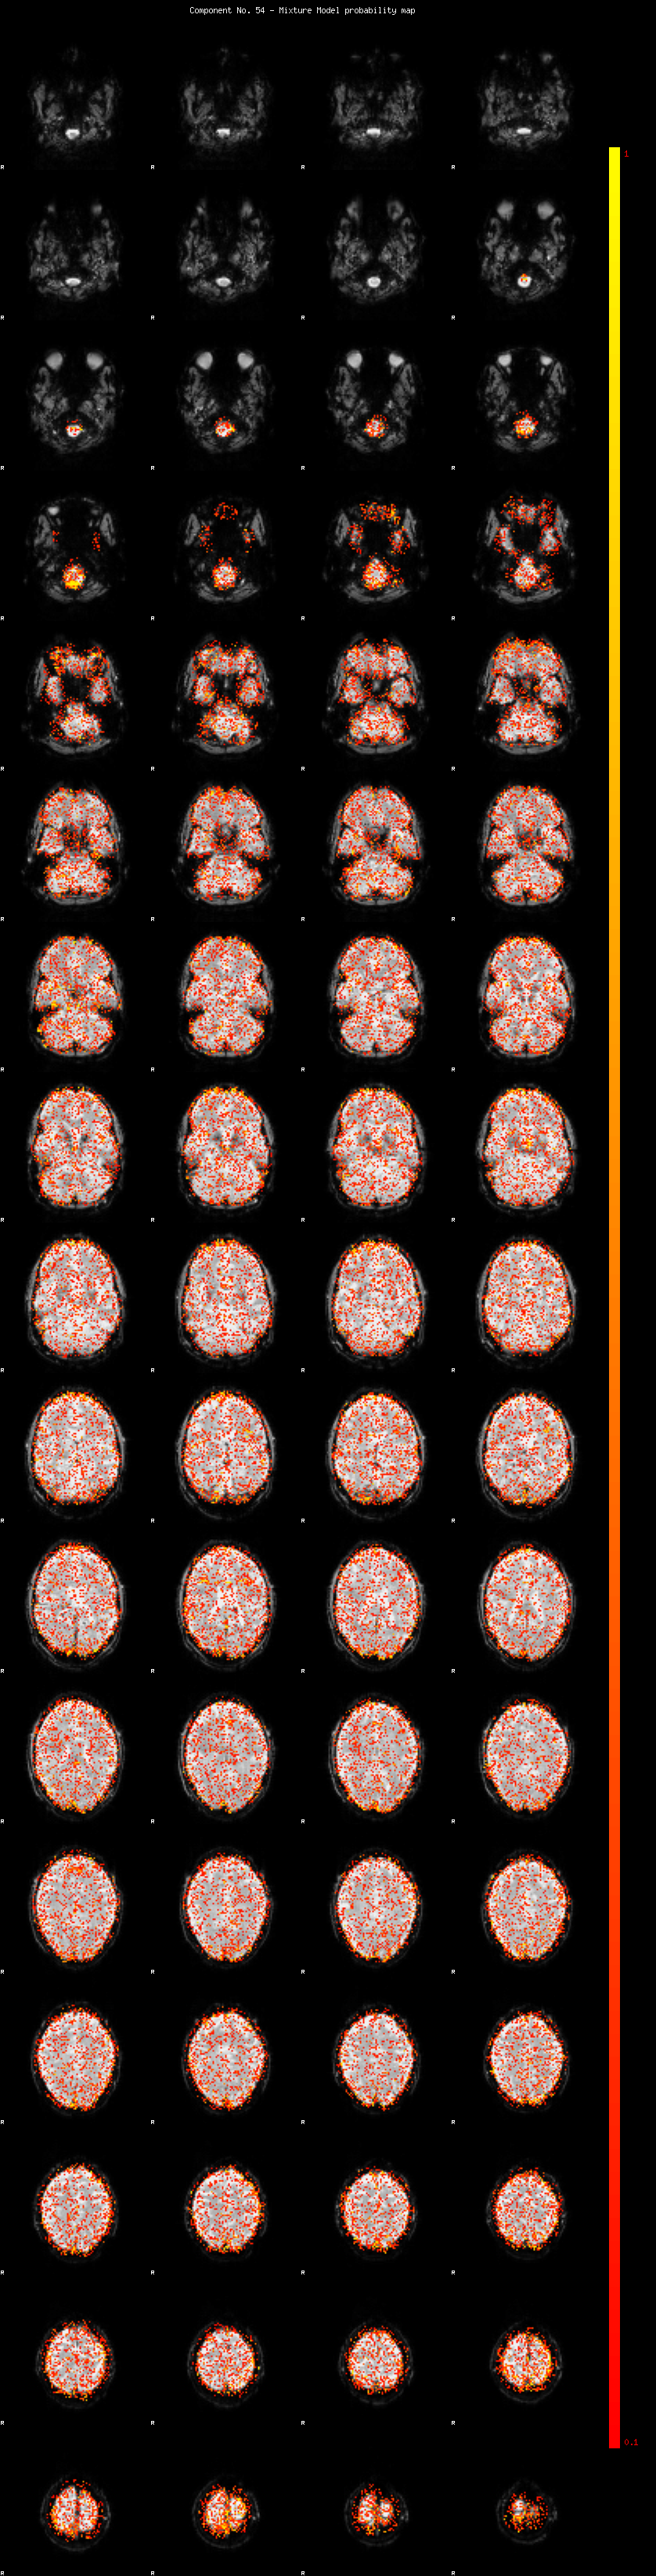

IC_54 Mixture Model fit

Means : -0.000000 2.078249 -2.066718

Vars : 1.000000 0.786181 0.774674

Prop. : 0.904180 0.053058 0.042762